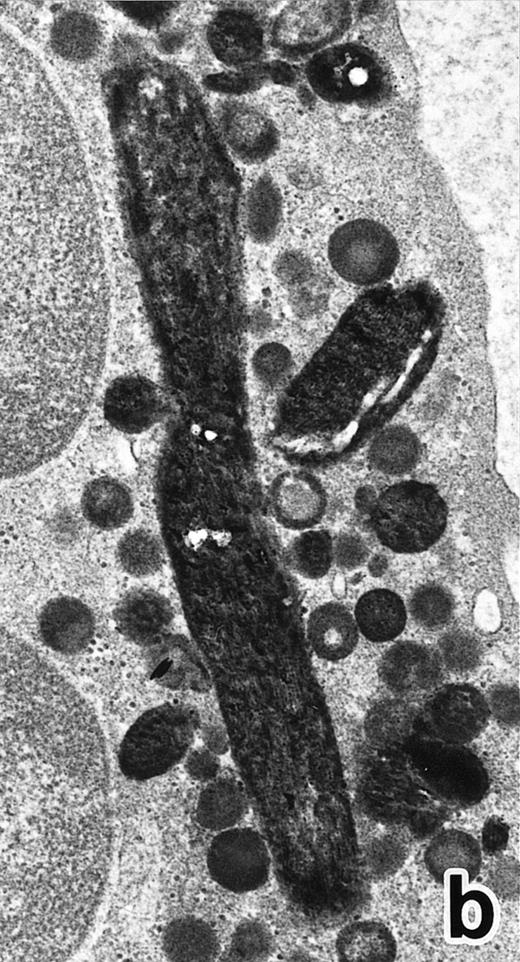

(a) A PMN in patient no. 1, seen in the bone marrow after 3 weeks of ATRA treatment. Lobulated nuclei are connected by nuclear filamentous structures and heterochromatin is highly condensed along the nuclear membrane. An Auer rod (A) is present along with primary granules. (Original magnification × 16,900.) (b) Higher magnification of the cytoplasm of a PMN in patient no. 3 after 3 weeks of ATRA treatment. Auer rods and cytoplasmic granules are all positive for MPO, and no MPO-negative secondary granules are evident. (MPO-stained section, original magnification × 41,900.)

After 2 to 3 weeks of ATRA treatment, maturation of leukemia cells progressed further, and cells resembling normal PMNs appeared (Fig 5). These cells contained multilobulated nuclei with marginally condensed heterochromatin and glycogen particles, characteristic of normal mature neutrophils. rER and free ribosomes became rare as the maturation process proceeded. However, these cells were still rich in primary (type I) granules, which somewhat varied in size and shape, including small and/or elongated forms. A small number of ellipsoid type II primary granules with a nucleoid structure were occasionally observed in patients no. 1 and 2, but not in patient no. 3. Conversely, MPO-positive, small, possibly type III, primary granules were rarely observed intermingled among the larger primary granules in maturing neutrophils in patient no. 3 alone. Despite the ultrastructural features otherwise characteristic of normal mature PMNs, specific granules, which are electron-lucent, elongated or dumbbell-shaped small granules, were not present in the majority of these PMN-like cells, as clearly shown by electron-microscopic cytochemical staining for MPO (Fig 5). The cells contained only MPO-positive primary granules and no MPO-negative secondary granules. A few abnormal primary granules, including Auer rods or C-H type granules, were still present in some cells, and these cells too were consistently devoid of specific granules (Fig 6). Another unusual finding in PMN-like cells at this stage was the presence of large spherical lipid droplets (Fig 5a), which may indicate altered physiological metabolism in these cells,29 because lipid droplets are usually not seen in normal PMNs. Although few in number, PMNs having both primary and secondary granules were also observed (Fig 7), and less mature intermediate forms with indented single nuclei or irregularly lobulated nuclei and numerous primary granules were still present at this stage of ATRA treatment.

The key findings in the present electron microscopic study of APL cells during the process of ATRA-induced differentiation are summarized as follows. (1) ATRA induced maturation of nuclei, namely, nuclear lobulation and marginal condensation of heterochromatin, resulting in generation of nuclei of mature neutrophils, although they were irregularly shaped with occasional nuclear blebs and very often connected by nuclear filamentous structures (filamentous connections)13 that appeared to be of pathologic significance, similar to the nuclear blebs reported in AML.20 30 (2) The majority of aberrant primary granules, including Auer rods, lost their abnormal contour in response to ATRA administration, although small numbers of PMNs with Auer rods or C-H type abnormal granules persisted throughout ATRA treatment. (3) The PMNs that emerged in the bone marrow of APL patients during ATRA treatment, particularly at an early stage, and in cultures of APL cells with ATRA were devoid of neutrophil secondary granules.